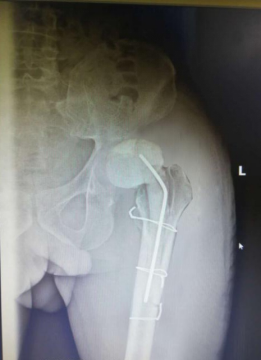

安放骨水泥旷置器后

经过6天的抗感染治疗后,患者的感染得到控制。2019年12月26日,张先生被送入了手术室,骨科汪军副主任医师与吕彬林主治医师先为张先生行“人工髋关节旷置术”,整个手术用时约3个小时,感染的人工关节假体被顺利取出。并使用双氧水、0.9%生理盐水、聚维酮碘反复冲洗后放入万古霉素骨水泥间隔器占位旷置。

术后继续使用万古霉素抗感染4周后,,张先生拆线出院。出院时,吕医生告诉他手术还尚未完结,要求他遵医嘱每月到我院门诊复查炎性指标及DR摄片,并在医生指导下进行功能锻炼。